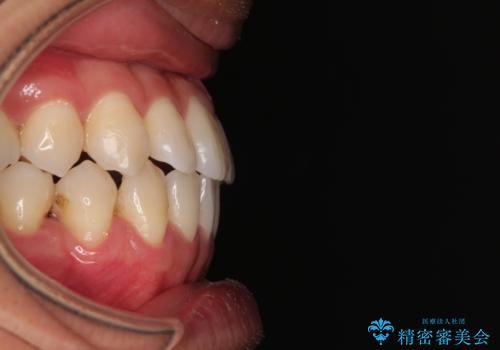

- 上下前歯部のデコボコを主訴として来院された患者様です。

上顎の歯列弓が下顎に対して狭いため、臼歯のかみ合わせがが咬頭対咬頭の状態です。

上顎の急速拡大装置を使用して、上顎骨を側方に拡大することで上顎歯列弓を拡大し、それに伴い下顎歯列弓も拡大できるようにして、歯列を整えていくこととしました。